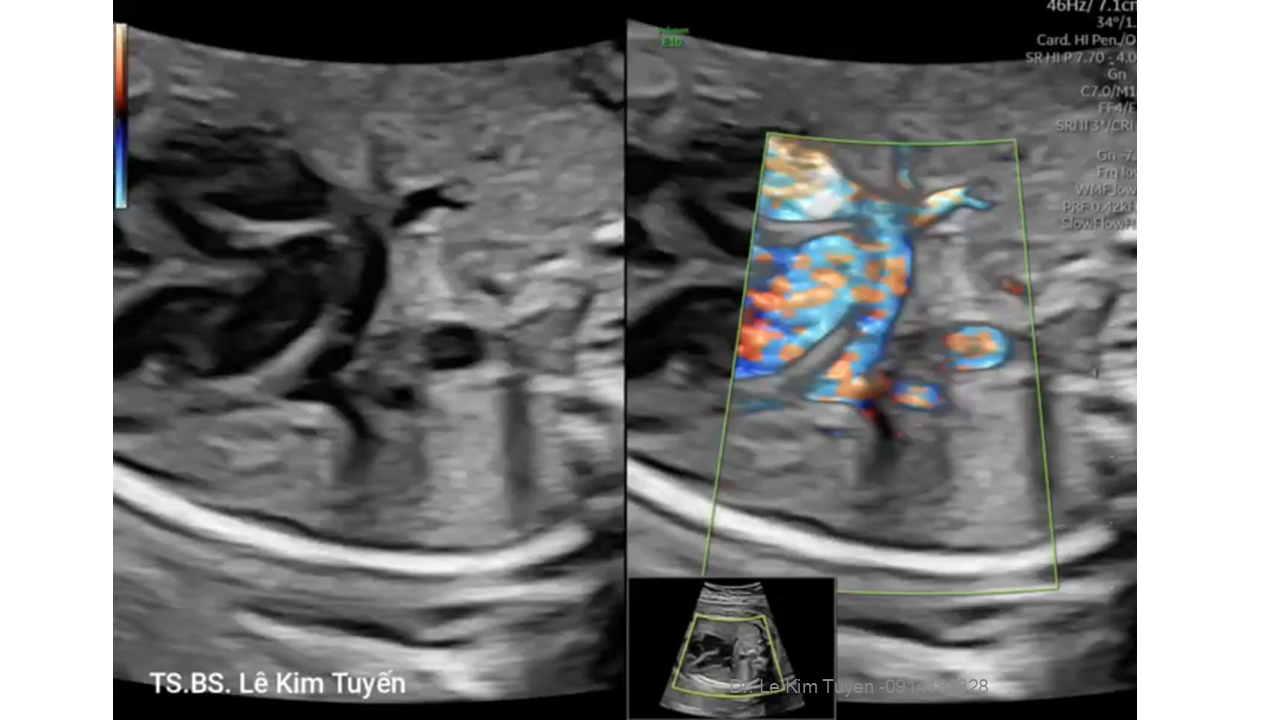

Áp dụng công nghệ Graphicflow trong phát hiện bệnh tim bẩm sinh cần cấp cứu sơ sinh

TS. BS. Lê Kim Tuyến

Bệnh viện Tim Tâm Đức